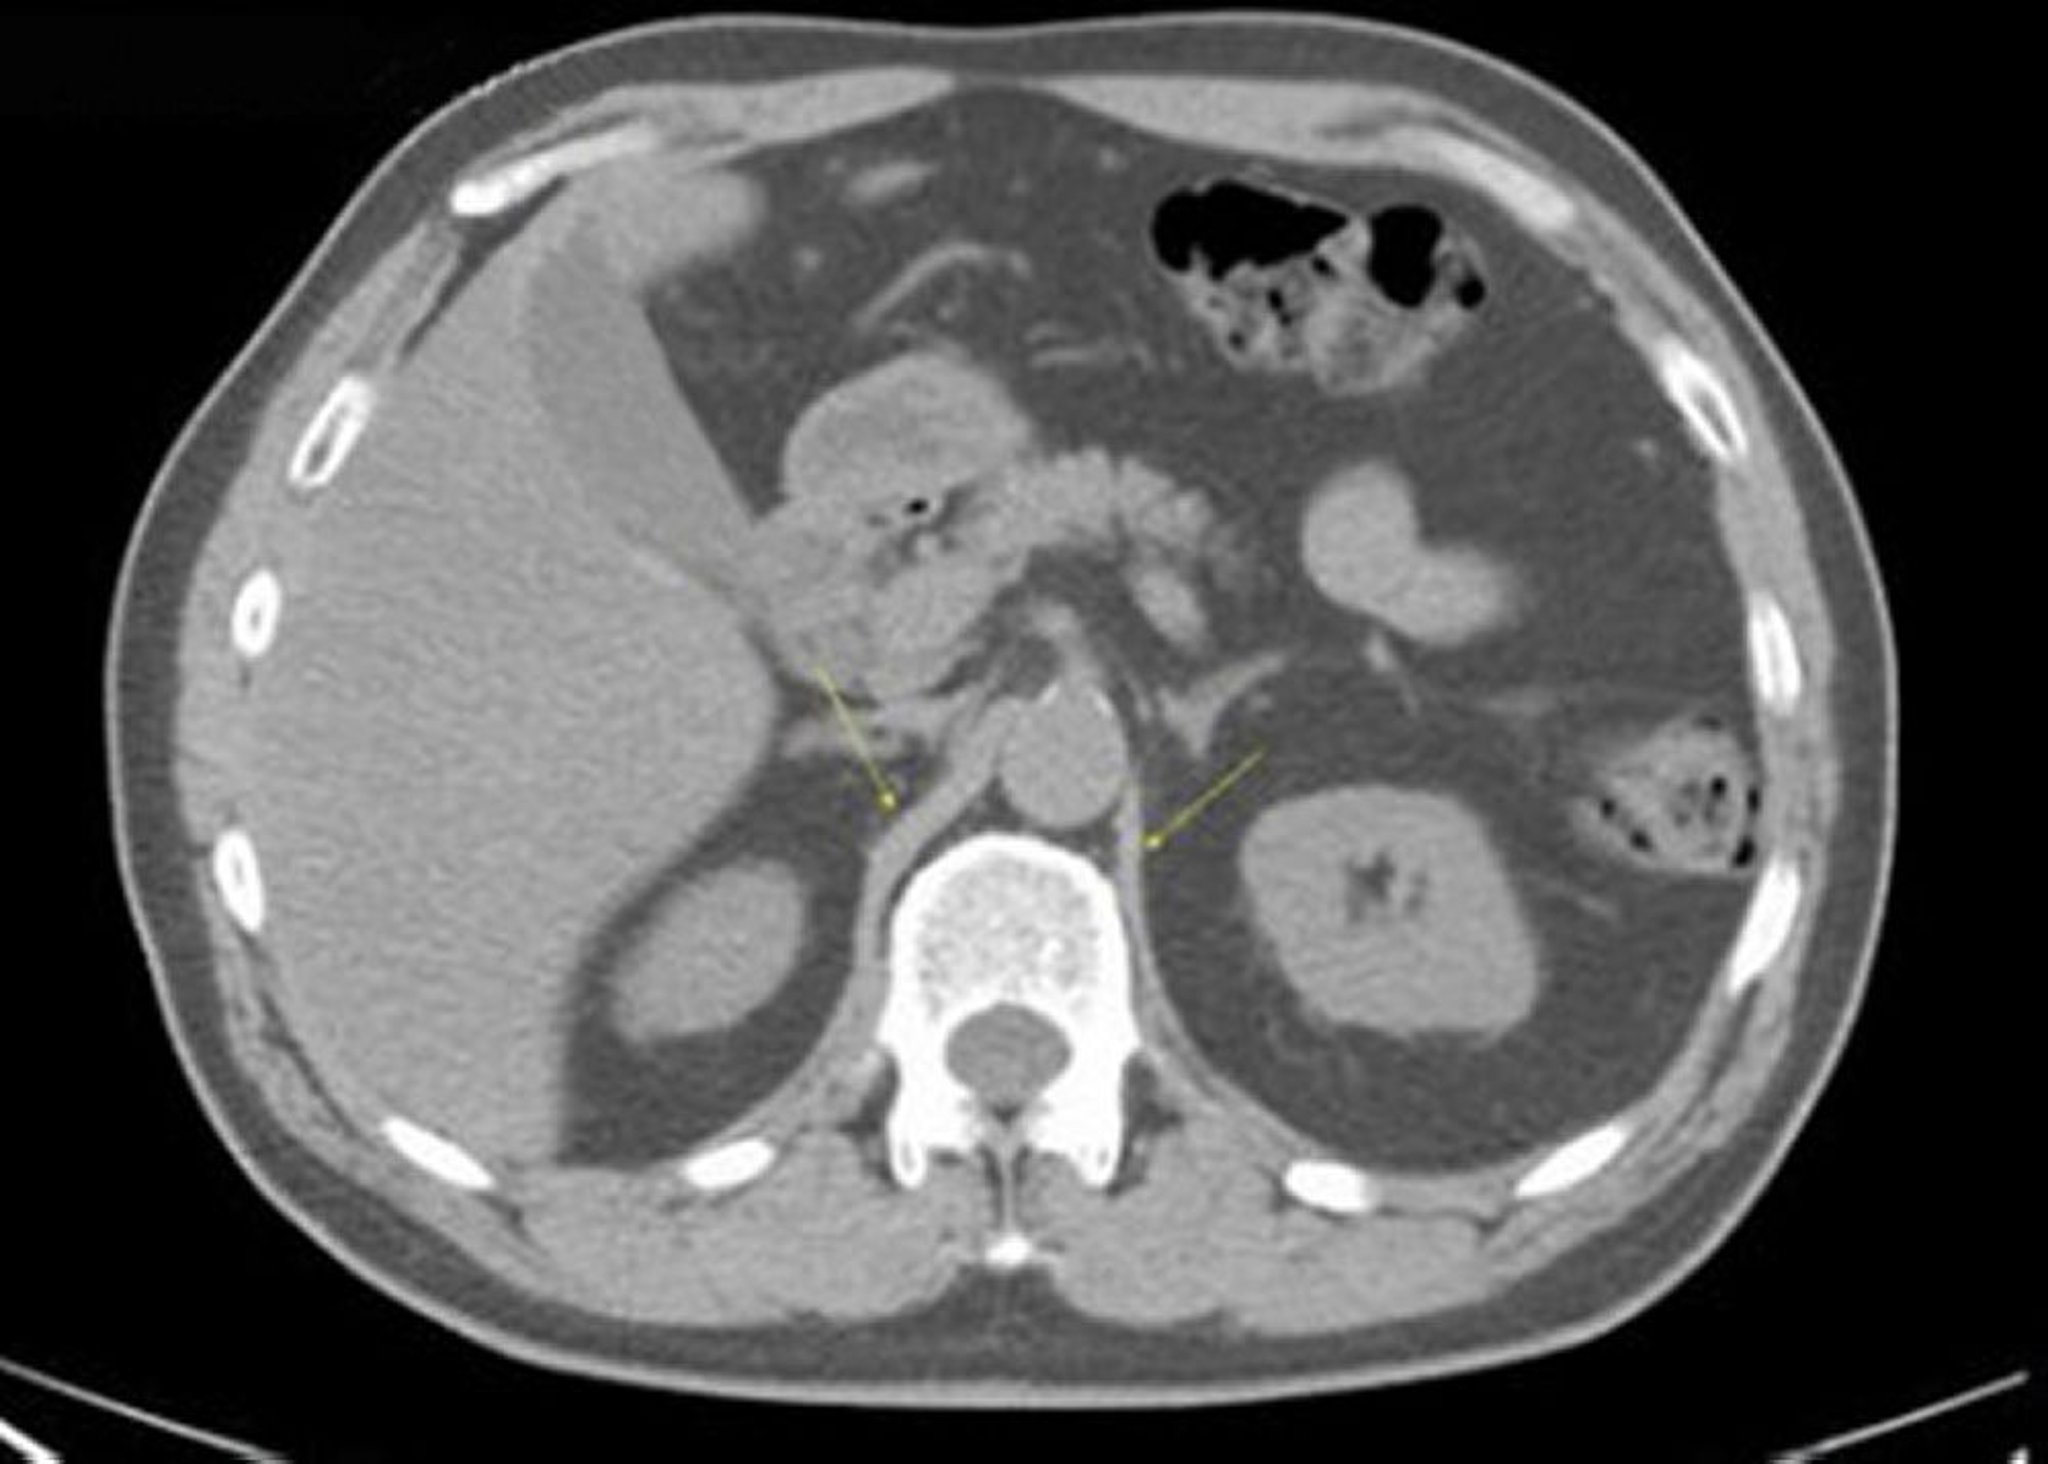

TC sem contraste do abdome e da pelve mostrando anatomia normal (lâmina 10)

Essa imagem mostra a crura do diafragma (setas).